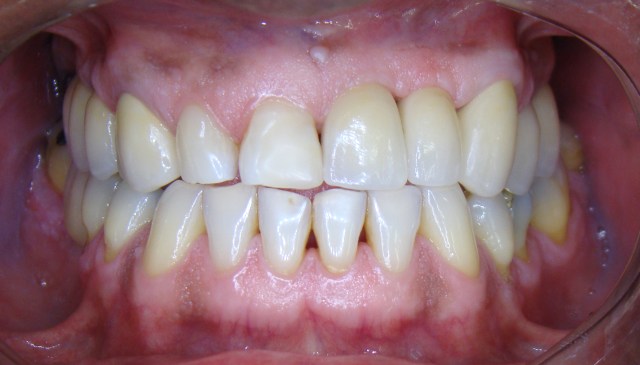

Neste caso o paciente apresentava algumas ausências dentárias e algumas coroas meta...